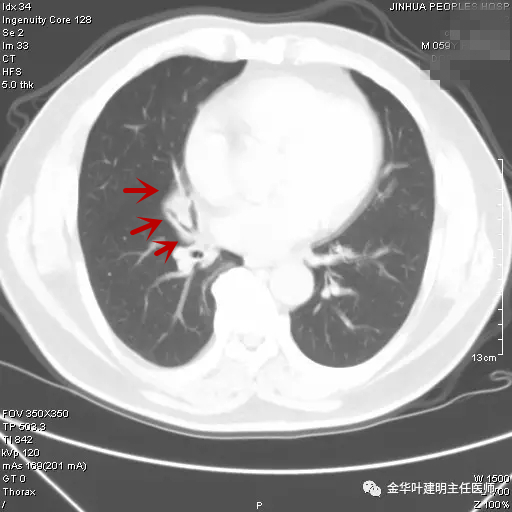

当时嘱其短期复查。后于次年的3月份回院来复查,CT表现如下图:

图三示:次年3月时复查的胸部CT肺窗

可见病灶与4个月前的影像表现相仿,并无明显改善,也无显著进展。但呼吸内科及胸外科医生没有局限于现有的诊断,因为其4个月以来,病灶没有任何好转,中叶支气管壁毛糙,仍怀疑不一定仅慢性炎症,需要进一步检查。经过与患者沟通后,决定行纤维支气管镜检查。结果正如医生所担心的,纤支镜提示:右肺中叶可见草莓样新生物,中叶开口粘膜累及 。活检病理:鳞癌。遂经过术前准备,排除手术禁忌证后,转来胸外科由叶建明与谭海栋为其进行了全麻下“胸腔镜下右肺中下叶切除及纵隔淋巴结清扫术”,手术顺利,术后病理示:右中叶中分化鳞癌,累及中叶支气管开口,中间支气管切缘阴性,纵隔淋巴结未见癌转移。